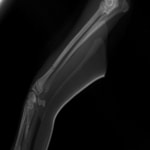

ペルシャ猫 11ヶ月齢 雄

他院にて左大腿骨遠位の成長板骨折(salter-harrisⅠ型)が認められており、治療相談を目的として来院。当院にて、キルシュナーワイヤーを用いたピンニングにより骨折部位の整復を行いました。術後の経過は良好で、現在も経過観察中です。

術前レントゲン